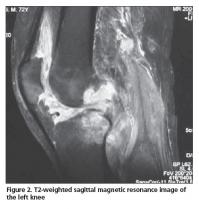

A 72-year-old male patient was admitted to our outpatient clinic with pain, swelling, and limited range of motion of the left knee, and difficulty in walking. His knee complaints had begun suddenly 1 year ago and he also had intermittent right hip joint pain. He had 1 hour of morning stiffness and his symptoms were slightly reduced by activity. He did not have any episodes of infections prior to symptom onset. He did not report fever, weight loss or sweating, and his rheumatologic history was uneventful other than his joint complaints. Despite the use of several non-steroidal anti-inflammatory drugs, there was no improvement in his knee pain, swelling, and range of motion. The anamnesis of the patient was unremarkable except he was treated for pulmonary TB 50 years ago and underwent surgery on his right hip due to trochanteric bursitis 3 years ago. On physical examination swelling and limited range of motion was observed in left knee. After activity, pain and increased temperature was also noted. His right hip joint motion was mildly painful without any limitation. Laboratory investigations revealed a white blood cell count of 6200/uL (normal range; 4800-10800/uL), hemoglobulin level of 12.8 mg/dL (normal range; 12-17 mg/dL), platelet count of 630.000/uL, erythrocyte sedimentation rate of 59 mm/h (normal range; 0-20 mm/h), blood glucose level of 110 mg/dL (normal range; 70-110 mg/dL), a C-reactive protein level of 8.99 mg/dL (normal value; <0.3 mg/dL), RF level of 63.70 IU/mL (normal value; <19 IU/mL), and anti-CCP antibody as 21.8 U/mL (normal value; 0-5 U/mL). The synovial fluid examination revealed a white blood cell count of 16.200/uL and a blood glucose level of 12 mg/dL. Marginal erosions were noted on the radiograph of the left knee (Figure 1). The anteroposterior pelvic radiograph revealed a region of ossification lateral to the right hip joint corresponding to the trochanteric bursa region. Magnetic resonance imaging (MRI) of the left knee revealed extensive hyperintense synovial thickening and erosive changes within the joint cavity, including all knee compartments and the suprapatellar bursa on T2-weighted images (Figures 2, 3). On contrast-enhanced MRI evaluation, fields of necrosis associated with infection showing peripheral enhancement were observed. Bone and joint pathologies defined in these investigations were compatible with infection. The differential diagnosis included arthritis, osteomyelitis, and especially TB, thus the Departments of Infectious Diseases, Chest Diseases, and Orthopedics were consulted. The Department of Infectious Diseases recommended that two consecutive joint aspiration samples should be screened for acid-resistant bacilli (ARB). Indeed, ARB were detected in both joint aspiration fluid samples. On lung tomography, as recommended by the Department of Chest Diseases, revealed fibrotic scars in the bilateral upper lobes, which were thought to be secondary to previous infection. Arthroscopic debridement was performed by the Department of Orthopedics and the biopsy result was compatible with a granulomatous inflammatory reaction. The patient was diagnosed with TB arthritis and treated accordingly. Clinical and laboratory improvement was noted on follow-up.